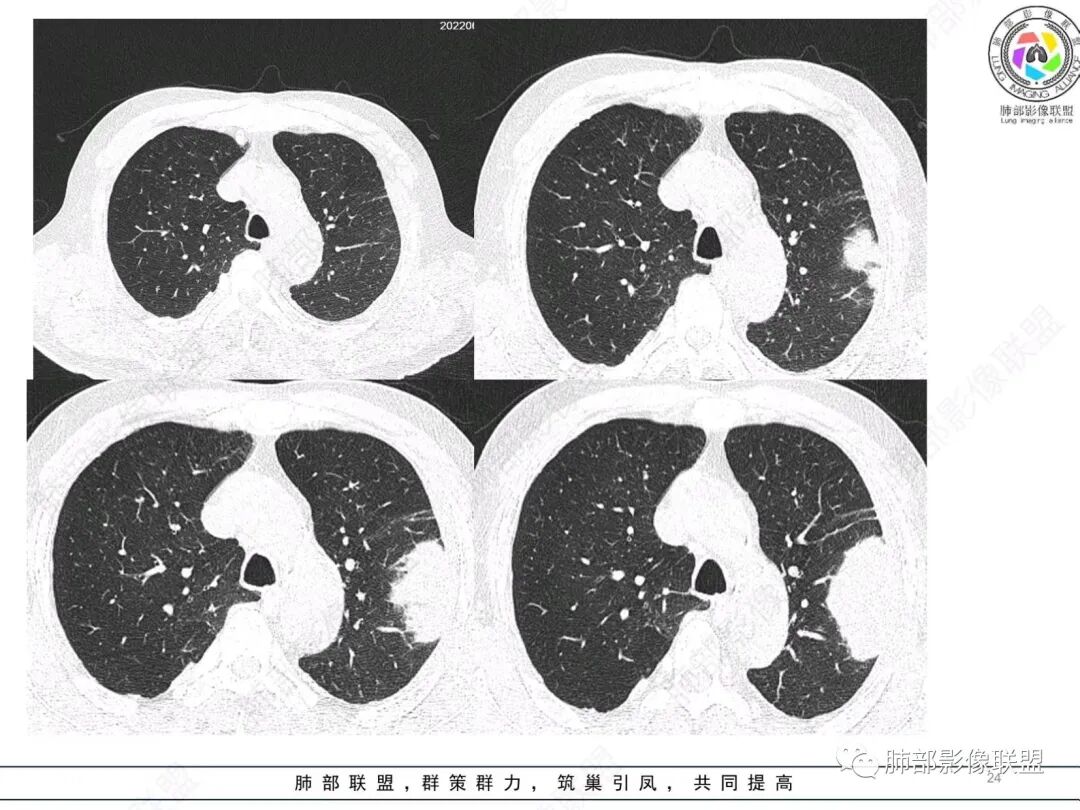

左肺上叶大肿块,膨胀性生长,边界清,密度较低,见部分坏死区,强化弱,肿块见支气管充气V扩张征,分布僵直,枯树枝特点,另一个重要特点血管造影征,淋巴瘤,肿块长轴与胸膜平行,与隐球菌鉴别,隐球荚膜抗原检查,明确诊断经皮肺穿刺。另胸膜钙化(问诊既往有无患胸膜炎病史)。

老年男性,糖尿病病史,消瘦、乏力三个月,影像表现左肺上叶胸膜下团块,有一定张力,内部疏松,可见支气管影及坏死区,增强病灶边缘环形强化,内部未见强化,考虑炎性肉芽肿病变,隐球?奴卡?放线菌?鉴别淋巴瘤。

左肺上叶胸膜下肿块,宽基底与胸膜相连,跨叶裂,边缘清晰膨隆,其内支气管充气,部分扩张、僵直,无明显强化,血管造影征,考虑淋巴瘤,鉴别腺癌

左肺上叶胸膜下肿块,膨胀性生长,边界清晰,密度不均部分坏死,未见强化,病灶内支气管迂曲扩张,病灶长轴与胸膜平行,胸膜下脂肪间隙存在,胸膜钙化,考虑放线菌?毛霉?鉴别淋巴瘤

糖尿病史,慢性病程,左肺巨大肿块,跨叶生长,肿块近端可见充气支气管征及悬浮气泡,轻度圴匀强化,病变长轴与胸膜平行,炎性标志物正常,考虑放线菌,其次淋巴瘤

1)部位:周围型或中央型软组织肿块,以周围型为多见,且肿瘤多位于肺上叶。如本例:该肿瘤位于左肺上叶。

3)肿块边界和边缘:多较清楚,呈圆形、类圆形,且由于肿块生长速度不均匀,可见分叶,毛刺少见。有报道肿块周围毛玻璃影是多形性癌特征表现。

4)密度:肿块平扫为软组织密度,由于体积较大,内部常见大片状坏死,可出现不规则厚壁空洞或坏死内多发无壁小空洞,坏死多不均匀:坏死灶内可见如柳絮样的斑片样强化灶,坏死边缘与非坏死区分界不清本例坏死较明显,密度不均匀。